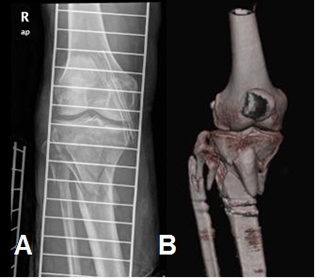

La principal indicación para realizar tomografía axial computarizada (TAC), es el trauma. Las reconstrucciones 3 D de fracturas en los platillos tibiales, son de mucha utilidad para la caracterización y planeación quirúrgica. (Fig 8).

Fig 8. Reconstrucción 3D.

A: Rx AP y B: TAC reconstrucción 3D. Fractura conminuta del tercio proximal de la tibia y el peroné.